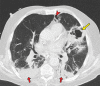

Chest CT has a potential role in the diagnosis, detection of complications, and prognostication of coronavirus disease 2019 (COVID-19). Implementation of appropriate precautionary safety measures, chest CT protocol optimization, and a standardized reporting system based on the pulmonary findings in this disease will enhance the clinical utility of chest CT. However, chest CT examinations may lead to both false-negative and false-positive results. Furthermore, the added value of chest CT in diagnostic decision making is dependent on several dynamic variables, most notably available resources (real-time reverse transcription-polymerase chain reaction [RT-PCR] tests, personal protective equipment, CT scanners, hospital and radiology personnel availability, and isolation room capacity) and the prevalence of both COVID-19 and other diseases with overlapping manifestations at chest CT. Chest CT is valuable to detect both alternative diagnoses and complications of COVID-19 (acute respiratory distress syndrome, pulmonary embolism, and heart failure), while its role for prognostication requires further investigation. The authors describe imaging and managing care of patients with COVID-19, with topics including (a) chest CT protocol, (b) chest CT findings of COVID-19 and its complications, (c) the diagnostic accuracy of chest CT and its role in diagnostic decision making and prognostication, and (d) reporting and communicating chest CT findings. The authors also review other specific topics, including the pathophysiology and clinical manifestations of COVID-19, the World Health Organization case definition, the value of performing RT-PCR tests, and the radiology department and personnel impact related to performing chest CT in COVID-19. ©RSNA, 2020.